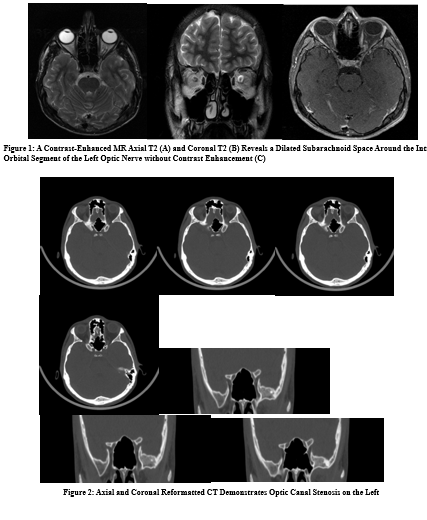

A 17-year-old boy presented with impaired visual acuity and blurred vision in the left eye. His complaints started one year ago. There was no prior history of malignancy, surgery, or trauma. Results of an ophthalmological examination revealed that his left- sided visual acuity had decreased to 0.4 and could not be corrected; visual acuity in his right eye was normal. A fundus examination conducted by an ophthalmologist revealed left-sided optic atrophy in the macula lutea region. The patient underwent to magnetic resonance imaging (MRI) to exclude intracranial pathology. A contrast-enhanced MR reveals a dilated subarachnoid space around the intra-orbital segment of the left optic nerve without contrast enhancement. The cavernous sinuses were normal. There was no focal brain lesion. Computed tomography (CT) was suggested to evaluate of the optic canal and skull base bony structures. CT demonstrates severe narrowing of the left optic canal. The width at the center of the left optic canal was measured at 1.74 mm and 4.06 mm on the right. The length of the optic canal was measured at 1.29 cm and 1.30 cm respectively.

In the present case, the shape of the bilateral optic canal is cylindrical, and the whole segment of the left optic canal is stenotic. The subarachnoid space around the intraorbital segment of the optic nerve was dilated and there was no contrast enhancement which indicates the entrapment neuropathy and explains patient’s symptoms. We have decided that it is not physiological asymmetry, but narrowing or stenosis of the optic canal.